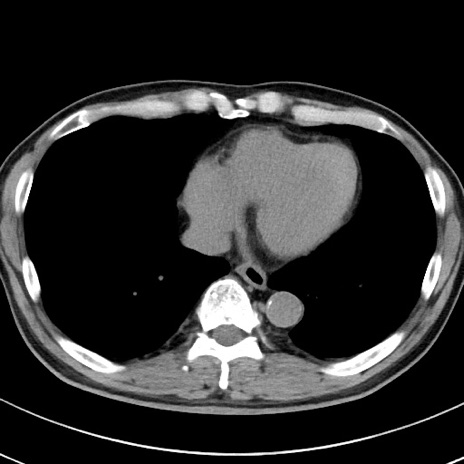

【腹部TIPS】症例29 参考症例 CT(横断像)

症例

70歳代男性